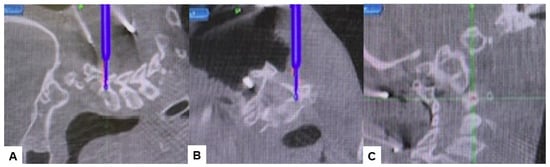

2.4. Surgery

2.5. Postoperative Imaging